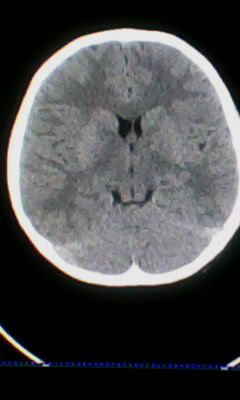

标题: PED3324:男 10岁 右侧 眼不自主抽动 自感颈部不适 [打印本页]

标题: PED3324:男 10岁 右侧 眼不自主抽动 自感颈部不适

蛛网膜下腔出血。

蛛网膜下腔出血可能。

颅脑ct轴位平扫颅内未见明确异常;建议必要时行mri检查。

窗调的不好,图像感觉怪怪的,不好说有什么明显异常,可建议mri检查。

颅脑ct轴位平扫颅内未见明确异常。